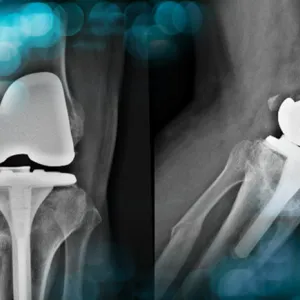

Discover the case of a 58-year-old man with a history of high tibial osteotomy, osteitis, and medial collateral ligament insufficiency, who underwent a total knee arthroplasty and experienced complications 6 months post-op. What kind of complication did the surgical team face, and how did they manage it?